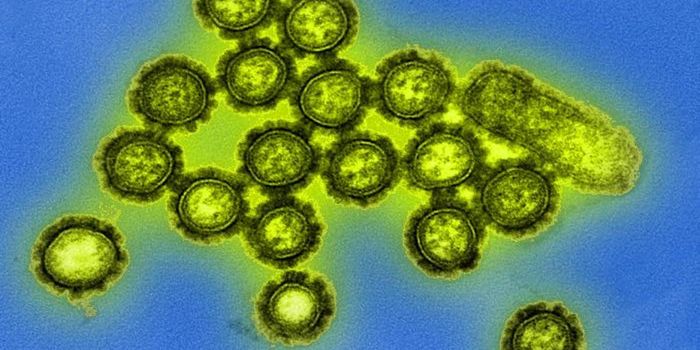

NOV 17, 2021MicrobiologyEvery year, there is a flu outbreak, and the severity can depend on many factors, like what strain is circulating. Last ...

MAY 25, 2021MicrobiologyThough suspected outbreaks have been documented since 1878, the first confirmed outbreak of bird flu, a highly pathogeni ...

APR 04, 2021MicrobiologyThere are many different influenza viruses, which cause from 290,000 to 650,000 deaths every year. That range depends on ...